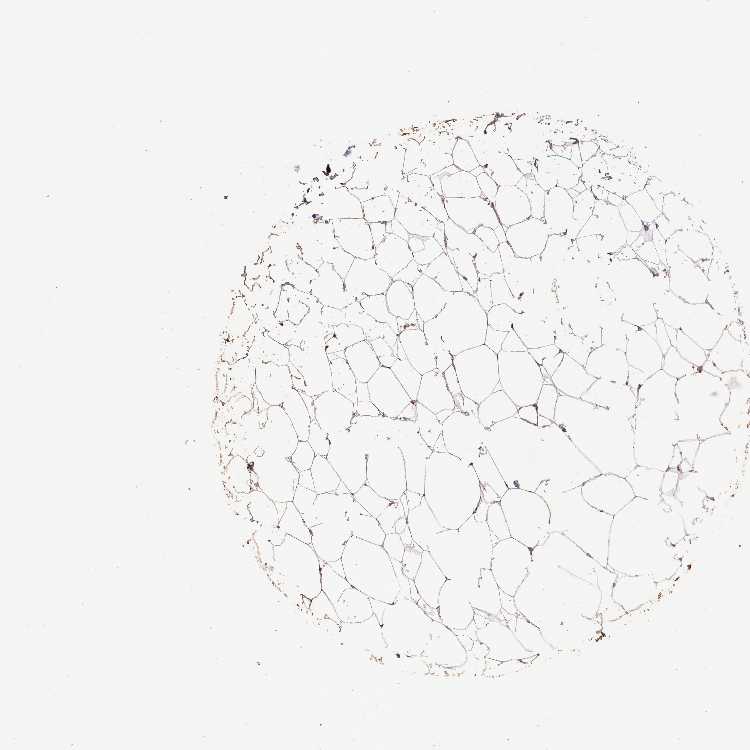

BREAST - Antibody stainingi

Antibody staining in the annotated cell types in the current human tissue is reported as not detected, low, medium, or high, based on conventional immunohistochemistry profiling in selected tissues. This score is based on the combination of the staining intensity and fraction of stained cells.

Each image is clickable and will lead to virtual microscopy that enables deeper exploration of all samples and also displays staining intensity scores, fraction scores and subcellular localization as well as patient and tissue information for each sample.

Antibody HPA065246

Adipocytes Low

Glandular cells Medium

Myoepithelial cells Medium